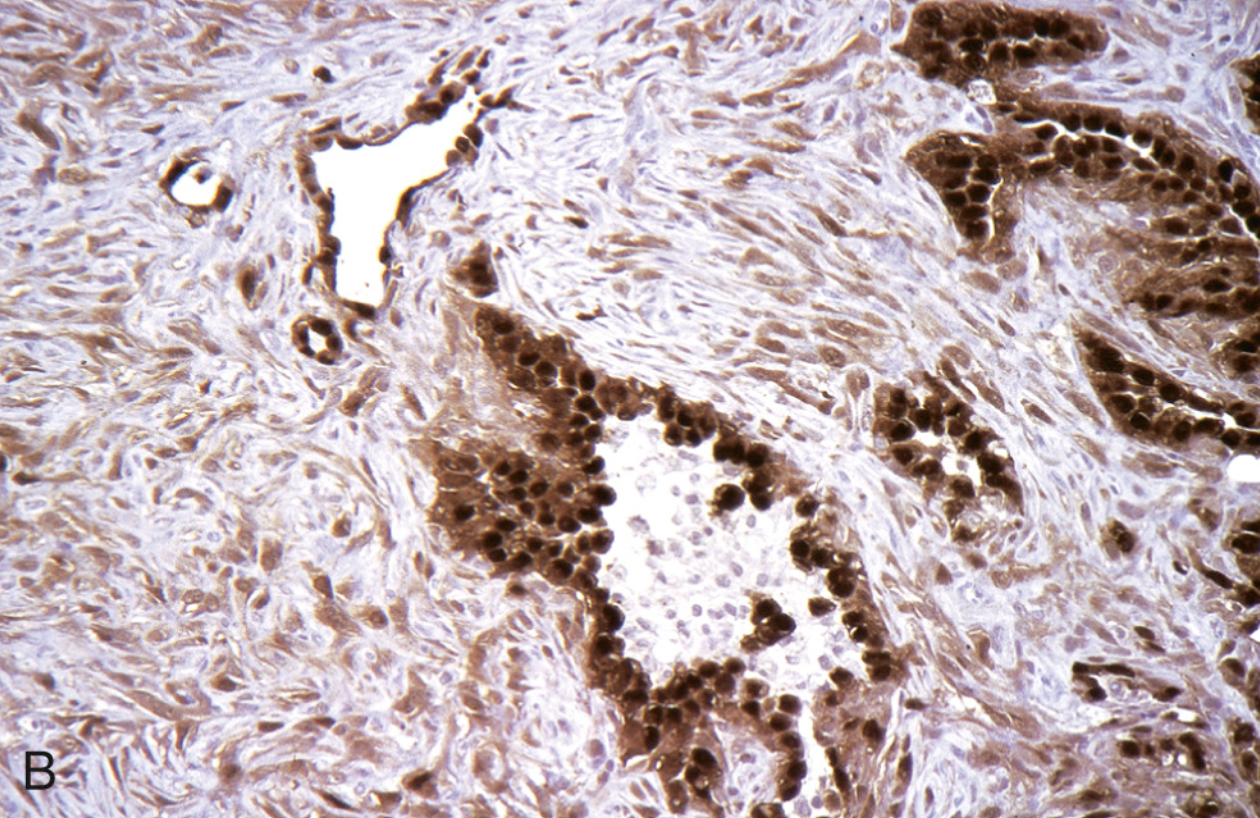

<p>Hiperplasia difusa idiopática de células <strong>neuroendocrinas</strong> pulmonares</p>

Hiperplasia difusa idiopática de células neuroendocrinas pulmonares

• Crecimiento nodular < 3mm

• Núcleos en sal y pimienta en zona basal